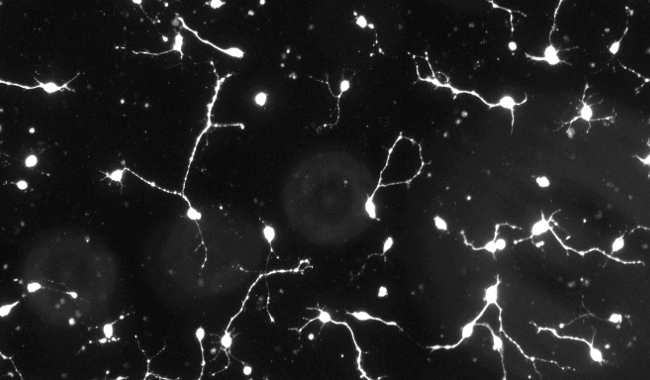

神經突增生圖像分析

神經系統是一個復雜的神經元網絡,它的正確運作高度依賴于神經元向神經元連接的適當發育;因此,神經回路的形成非常依賴于突起生長過程的正確進化。突起生長是神經突起形成和發展的復雜而關鍵的過程,其故障涉及一系列的神經元疾病和疾病,如阿爾茨海默病和帕金森,因此它構成了神經病學和精神病學研究的主要焦點之一。